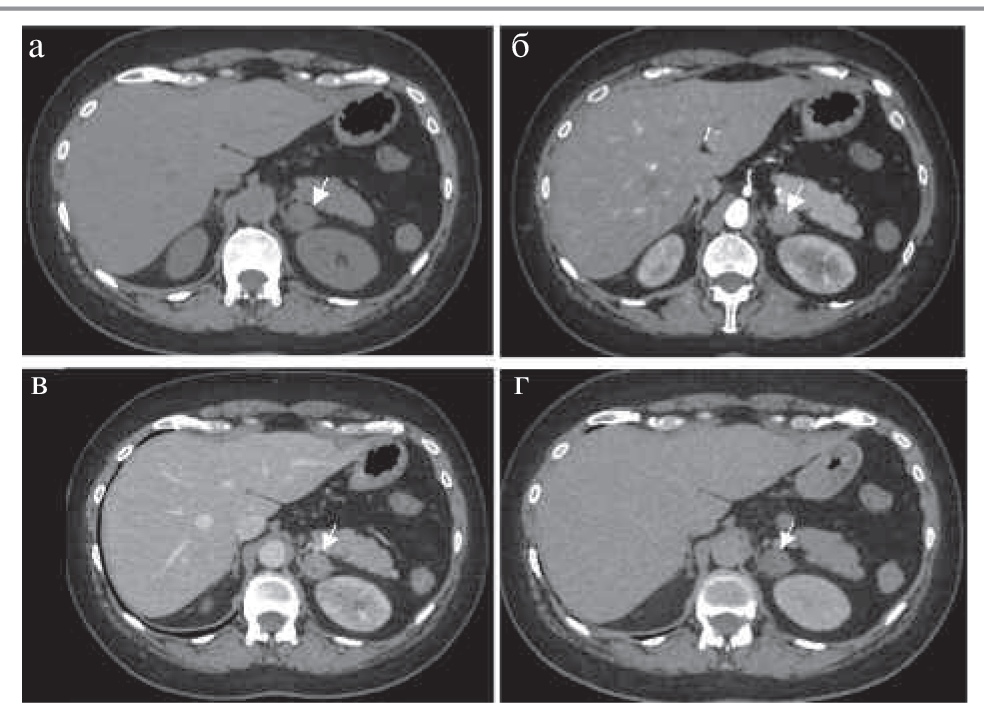

На КТ-изображениях аденомы обычно представляют собой образования с четкими ровными контурами овальной формы, однородной структуры, размером, как правило, менее 3 см. При динамическом наблюдении размер аденом не меняется или увеличивается в пределах нескольких миллиметров в год (рис. 2) [5].

Рис. 2. МСКТ, аксиальная проекция: а – НФ; б – АФ; в – ВФ; г – ОФ. Аденома надпочечника с низким содержанием жира (стрелка). Примечание. МСКТ – мультиспиральная компьютерная томография.

В зависимости от количества внутриклеточных жировых включений различают аденомы с высоким содержанием жира (80%) и с низким его содержанием (20%), что проявляется характерной КТ-картиной [7]. Так, аденомы с высоким содержанием жира представлены образованиями плотностью на нативных изображениях до 10–15 ед. Н.

Все аденомы имеют патогномоничное накопление контрастного препарата с быстрым «вымыванием» его после внутривенного болюсного контрастирования, что позволяет дифференцировать аденомы с остальными заболеваниями надпочечников.

Для оценки характера контрастирования в большинстве случаев проводится четырехфазное КТ-сканирование с болюсным введением неионного йодсодержащего контрастного препарата со скоростью 2–4 мл/с, дозой контрастного вещества с концентрацией 300–350 мг йода/мл (60–76%) не менее 1 мл/кг веса тела пациента (лучше – 100–140 мл). Исследование проводят в нативную фазу (НФ), артериальную фазу – АФ (18–25 с после начала введения болюса контрастного препарата или 10 с после достижения пика 100–150 ед. Н на болюс-трекере), венозную фазу – ВФ (55–65 с от начала введения болюса) и отсроченную фазу – ОФ (15 мин после введения контрастного препарата). Для аденом максимальное накопление контрастного препарата в большинстве наблюдений определяется в ВФ. Впервые оценку характера вымывания контрастного препарата в ОФ на различных минутах (от 5 до 15-й) при образованиях надпочечников описали в своей работе M. Korobkin и соавт., где выявили, что наиболее точные результаты получены при измерении плотности образования в ОФ на 15-й минуте [1].

Если APW более 60% (чувствительность и специфичность 88 и 96% соответственно) и RPW превышает 40% (чувствительность и специфичность 83 и 95% соответственно), объемное образование рассматривается как доброкачественное [2, 8].

Если APW менее 60% и RPW ниже 40%, то это признак, подозрительный на наличие злокачественной природы образования надпочечника [2, 7, 8].